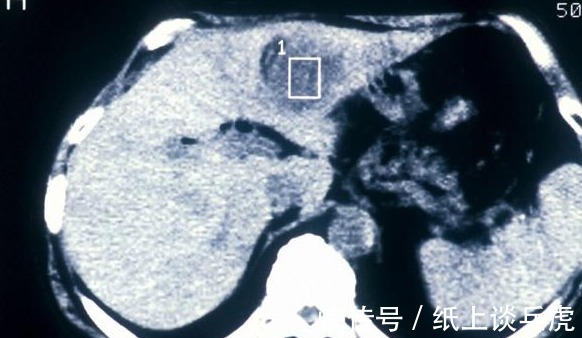

射频消融是一种局部微创治疗,在肝癌区域放置射频消融针,其前端有多个电极丝,当射频电流输出后,病灶区局部温度升高,癌细胞受热发生凝固坏死,进而达到治疗肝癌的目的。

文章插图